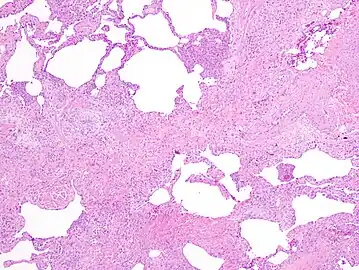

The histologic hallmarks of UIP, as seen in lung tissue under a microscope by a pathologist, are interstitial fibrosis in a "patchwork pattern", honeycomb change and fibroblast foci (see images below).[6] [7]

Appearance of usual interstitial pneumonia (UIP) in a surgical lung biopsy at low magnification. The tissue is stained with hematoxylin (purple dye) and eosin (pink dye) to make it visible. The pink areas in this picture represent lung fibrosis (collagen stains pink). Note the "patchwork" (quilt-like) pattern of the fibrosis. -